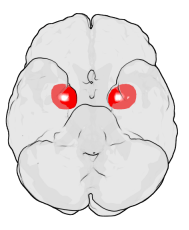

The amygdalae (singular: amygdala; /əˈmɪɡdələ/; also corpus amygdaloideum; Latin, from Greek ἀμυγδαλή, amygdalē, 'almond', 'tonsil'[1]) are two almond-shaped groups of nuclei located deep and medially within the temporal lobes of the brain in complex vertebrates, including humans.[2] Shown in research to perform a primary role in the processing of memory, decision-making, and emotional reactions, the amygdalae are considered part of the limbic system.[3]

The regions described as amygdala nuclei encompass several structures with distinct connectional and functional characteristics in humans and other animals.[4] Among these nuclei are the basolateral complex, the cortical nucleus, the medial nucleus, the central nucleus, and the intercalated cell clusters (ITCs). The basolateral complex can be further subdivided into the lateral, the basal, and the accessory basal nuclei.[3][5][6]